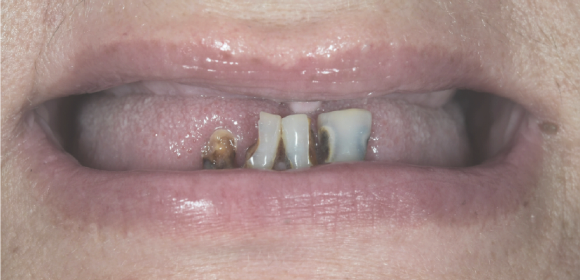

Metoda All-on-4 ® pozwala na przywrócenie pacjentowi pełnego uśmiechu i funkcji jamy ustnej nawet w ciągu jednego dnia, co jest szczególnie ważne w skomplikowanych przypadkach anatomicznych. Każdy plan leczenia jest dostosowywany indywidualnie do potrzeb pacjenta, uwzględniając jego oczekiwania biomechaniczne, estetyczne i funkcjonalne.

Gabinet oferuje pełen zakres usług wspierających proces leczenia, dzięki czemu możliwe jest dostosowanie procedury do unikalnych potrzeb każdego pacjenta. Wybór metody All-on-4 ® oznacza komfort, precyzję i trwałe efekty przy minimalnym czasie rekonwalescencji.

metamorfozy naszych pacjentów